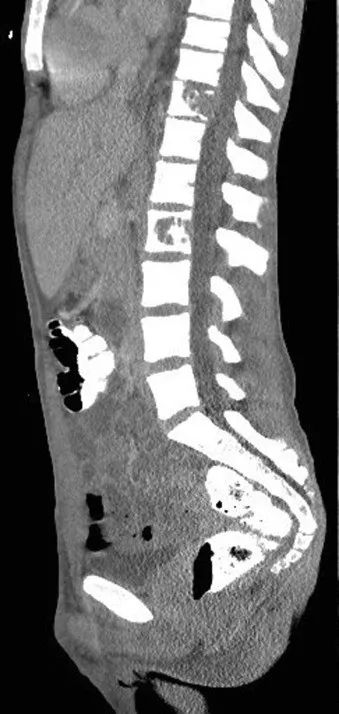

全血白细胞计数为13.4*109/L,血红蛋白8.5g/dL,血小板138/μL,C-反应蛋白28.8(正常值<3.0)。动脉血气分析显示pH值为7.30,PCO2为48.2,PO2为71.8,血培养呈阴性,进行BAL培养(包括细菌培养、病毒培养、真菌培养)。胸部X线及胸部CT显示弥漫性斑片状阴影(图1.2)。颈椎、胸椎和腰椎的CT扫描显示椎体病变(图3.4)。由于脾脏有多处病变,也进行了脾活检(图5)。

图3 颈椎/胸椎CT:C5椎体广泛透明、前路高度破坏约70%

图4 腰椎CT:T11和L2椎体破坏性病变